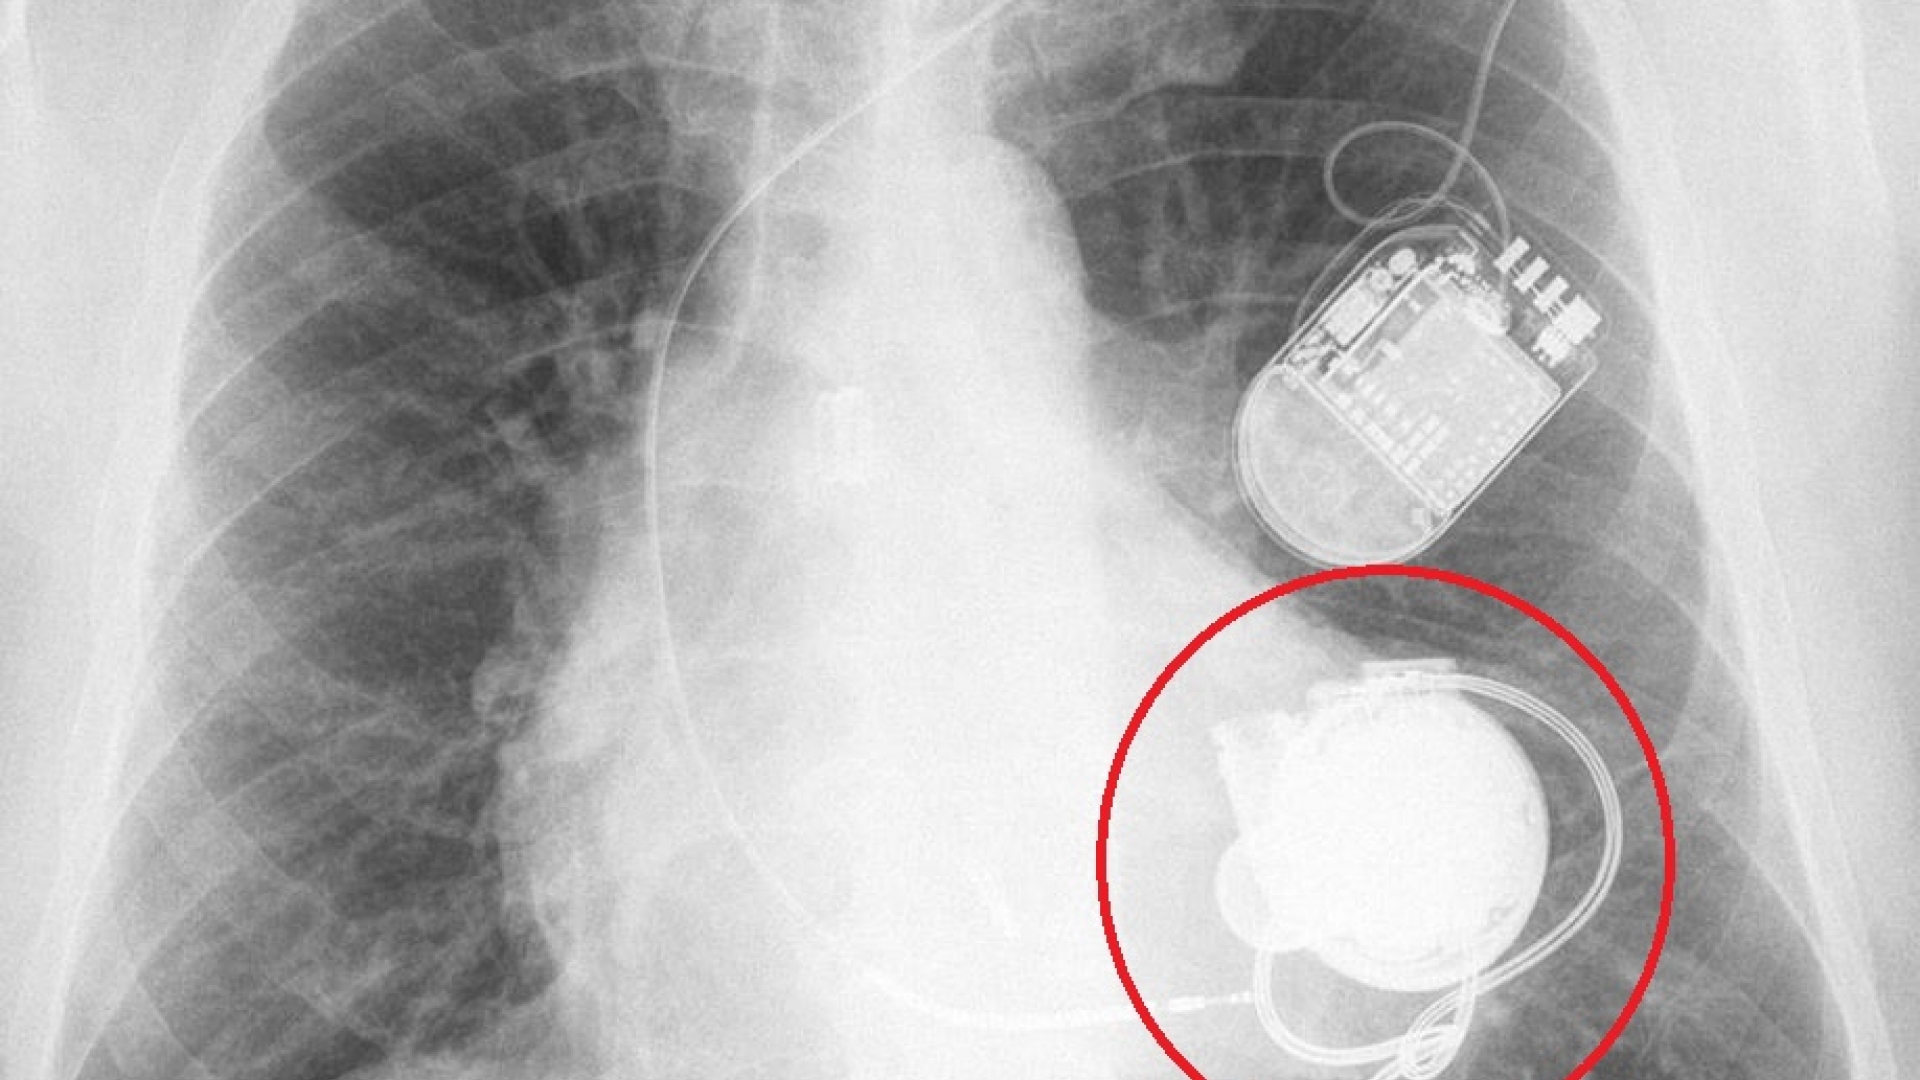

Das auf dem Röntgenbild erkennbare Kunstherz wurde in die linke Herzkammer eingesetzt und pumpt das Blut von dort in die Aorta. Darüber erkennt man einen Kardioverter-Defibrillator, der wegen lebensbedrohlichen Herzrhythmusstörungen zusätzlichen eingesetzt wurde.

Die Implantate sind über Kabel mit einer externen Kontrolleinheit und der Stromversorgung, meist zwei separaten Batteriepacks, verbunden.